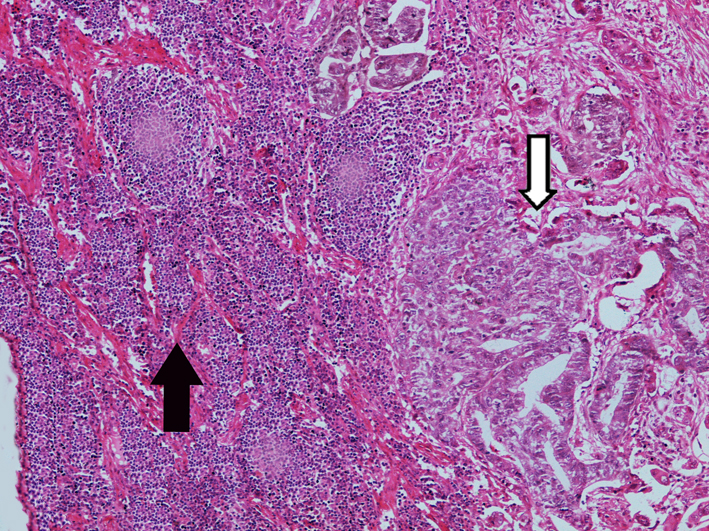

3.Metastatic adenocarcinoma in lymph node